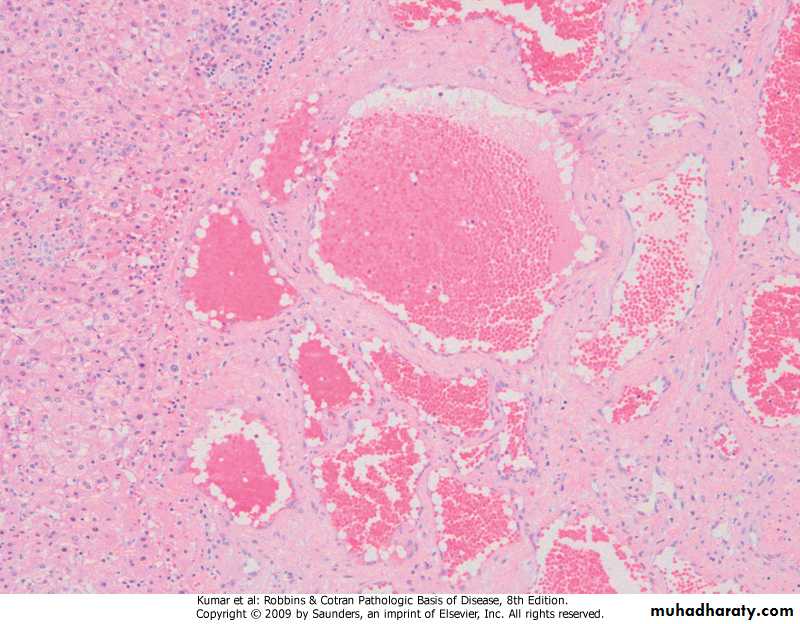

Focal Nodular HyperplasiaDefinition: It is a localized, well-demarcated consisting of hyperplastic hepatocyte nodules with a central, stellate fibrous scar.

It is not a true neoplasm but rather represents a response to abnormal vascular flow through a congenital or acquired vascular anomaly.

Gross yellowish with central gray-white, depressed stellate scar from which fibrous septa radiate to the periphery.Focal nodular hyperplasia

Focal nodular hyperplasia, hyperplastic hepatocyte nodules with a central fibrous septa contain dilated blood vessels and bile ducts.